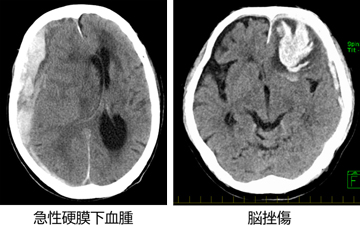

迅速に頭部CTによる検査を行い適切な対応により重症化を防ぎます。必要であればすぐに緊急手術を行います。術後は、神経モニタリングを用いた神経集中治療を行い考え得る最上の経過を目指します。急性期の治療後も、リハビリテーションや再生医療、外来診療を長期間行い、高次脳機能障害も含めて患者様の社会復帰を支援いたします。